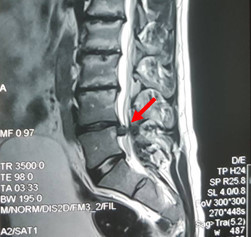

Հետաքրքրաշարժ է, որ նախքան վիրահատությունը ՄՌՏ հետազոտությամբ որևէ արտառոց պատկեր չէր արձանագրել և ախտորոշվել էր միջողային աճառի ճողվածք, ինչը պատկերված է ստորև: